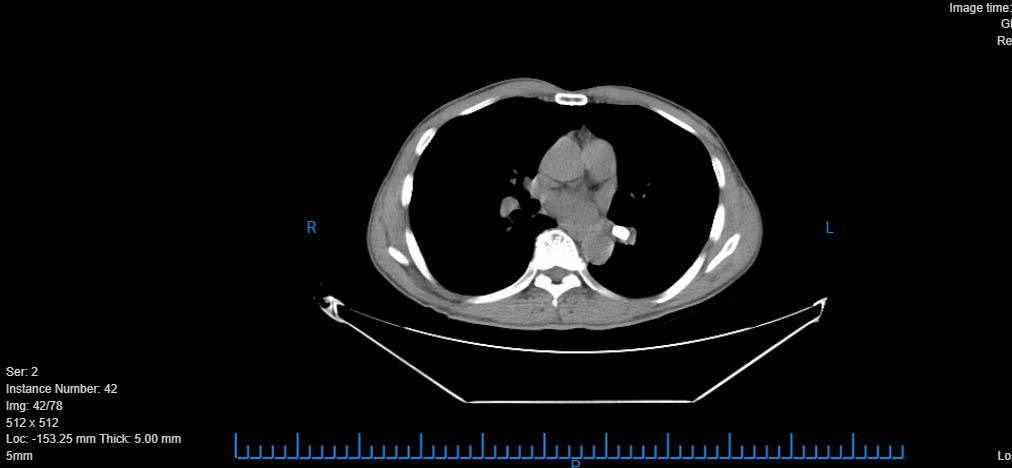

Bệnh nhân được bác sĩ thăm khám và xử trí ban đầu. Kết quả chụp CT ngực có tái tạo 3D phát hiện dị vật đường thở ở thùy dưới phổi bên trái, bệnh nhân nhanh chóng được tiến hành nội soi gắp dị vật có phối hợp chuyên gia Hà Nội. Quá trình thực hiện phát hiện, lòng phế quản có một phần viên thuốc, ekip đã tiến hành sử dụng rọ để lấy đồng thời tiếp tục bơm nước rửa nhiều lần và lấy nốt phần còn lại ra thành công. Sau gắp, bệnh nhân đã hết tức ngực, hết khó thở và ổn định.

- Hình ảnh chụp CT ngực của bệnh nhân